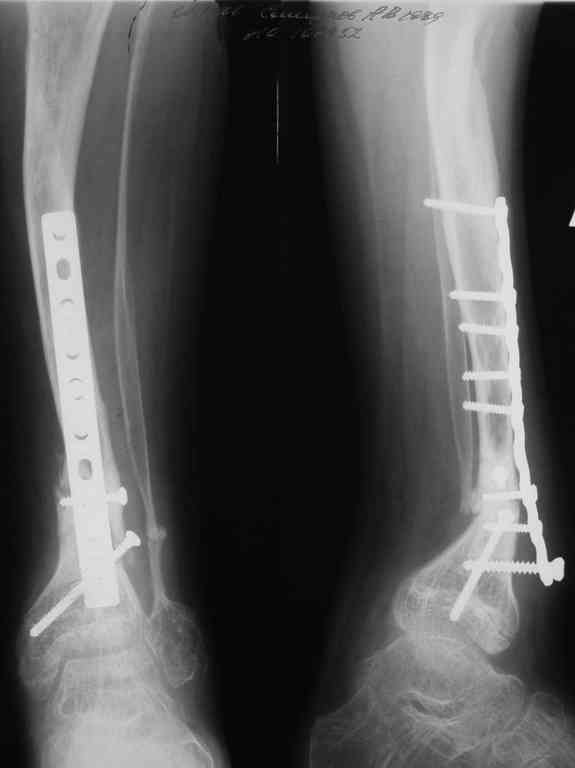

Уважаемые коллеги! В отделении на лечении наблюдается пациент 16 лет с диагнозом: Псевдоартроз костей левой голенив нижней трети. Вальгусная деформация обоих коленных суставов. Укорочение левой н/конечности11см. С 1997 года состоит на учёте у онколога с диагнозом: Рабдомиосаркома мышц тазового дна IV ст., с метастазами в метафизы берцовых костей.Проведена полихимиотерапия, лучевая терапия. В 1998 г. удаление опухоли. Послеоперационный период без особенностей. С 1998 года со стороны онкологии ремиссия, перестройка очагов метастазирования в берцовых костях по типу фиброзной дисплазии.В 1999 г. патологический перелом костей левой голени в н/трети. Лечение в гипсе 1.5 месяца, затем компрессионно-дистракционный остеосинтез апп. Илизарова. Сращения на месте псевдоартроза не достигнуто. С 1999г. ходит без нагрузки на левую н/конечность. Выраженный остеопороз костей н/конечностей. 17.11.05. Операция: Костная пластика зоны псевдоартроза левой б/берцовой кости по типу "русский замок", остеосинтез пластинкой и винтами. После начала нагрузки на конечность рецидив деформации, миграция фиксаторов. 05.12.06. Операция: Удаление фиксаторов из левой голени. Шарнирная остеотомия трети левой б/берцовой кости, остеотомия м/берцовой кости. Дистракционный остеосинтез апп. Илизарова. Устранены основные виды деформации б/берцовой кости. Планировали в дальнейшем несвободную костную аутопластику и интрамедуллярный остеосинтез с блокированием, но кость очень тонкая, склерозированная, выраженный остеопороз. Возникают большие сомнения о возможности сращения даже при этих условиях. Будем рады услышать ваши мнения по дальнейшему лечению данного пациента. Екатериан Анатольевна Озерова, детское отделение УНИИТО